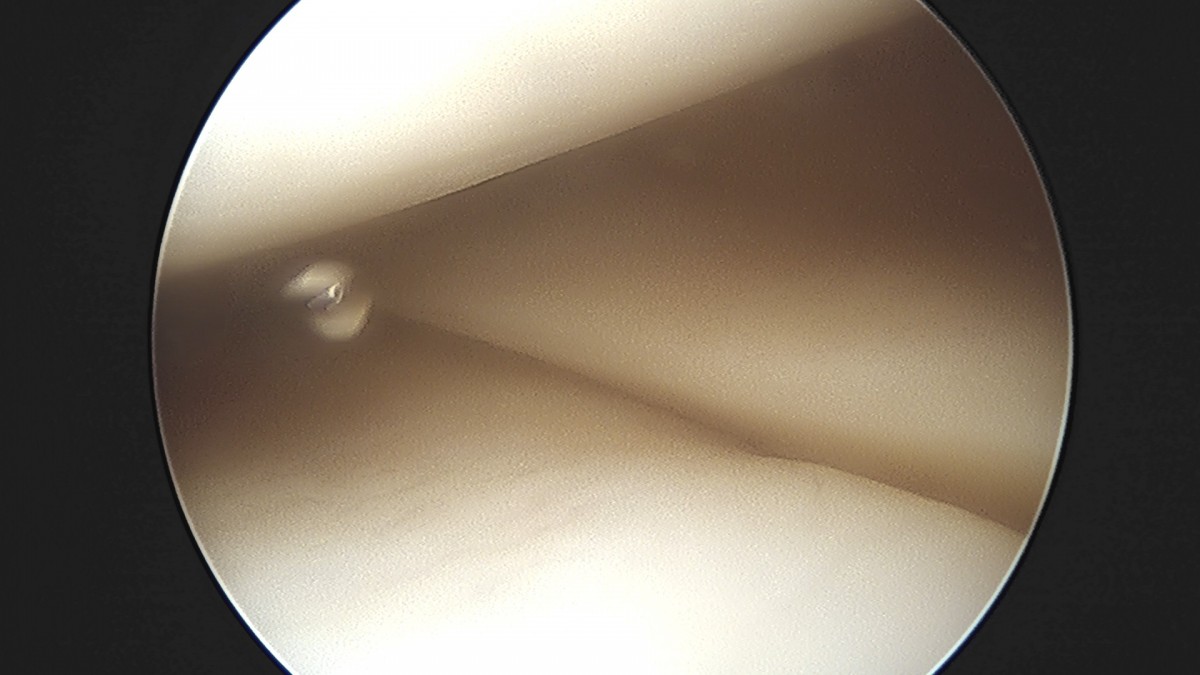

이재상원장님 무릎 전방십자인대 재건술 김태O 환자

작성자 최고관리자 댓글 0건 조회 679회 작성일 25-09-16 16:23